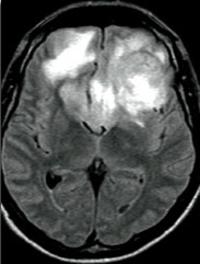

Le papillome inversé est une tumeur bénigne des fosses nasales qui se caractérise par la prolifération de cellules épithéliales en amas (papillome) vers le chorion sous-jacent : cette particularité est à l’origine du vocable inversé. Cliniquement, il entraîne le plus souvent une obstruction nasale unilatérale avec rhinorrhée. Le bilan complémentaire nécessite une IRM centrée sur les cavités sinusiennes et une biopsie. Le traitement est chirurgical et consiste en l’exérèse [...]